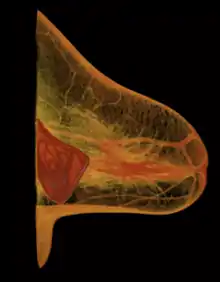

The five surgical approaches to emplacing a breast implant to the implant pocket are often described in anatomical relation to the pectoralis major muscle.

- Subglandular: the breast implant is emplaced to the retromammary space, between the breast tissue (the mammary gland) and the pectoralis major muscle (major muscle of the chest), which most approximates the plane of normal breast tissue, and affords the most aesthetic results. Yet, in women with thin pectoral soft-tissue, the subglandular position is likelier to show the ripples and wrinkles of the underlying implant. Moreover, the capsular contracture incidence rate is slightly greater with subglandular implantation.

- Subpectoral (dual plane): the breast implant is emplaced beneath the pectoralis major muscle, after the surgeon releases the inferior muscular attachments, with or without partial dissection of the subglandular plane. Resultantly, the upper pole of the implant is partially beneath the pectoralis major muscle, while the lower pole of the implant is in the subglandular plane. This implantation technique achieves maximal coverage of the upper pole of the implant, whilst allowing the expansion of the implant's lower pole; however, “animation deformity”, the movement of the implants in the subpectoral plane can be excessive for some patients.[89]

- Submuscular: the breast implant is emplaced beneath the pectoralis major muscle, without releasing the inferior origin of the muscle proper. Total muscular coverage of the implant can be achieved by releasing the lateral muscles of the chest wall—either the serratus muscle or the pectoralis minor muscle, or both—and suturing it, or them, to the pectoralis major muscle. In breast reconstruction surgery, the submuscular implantation approach effects maximal coverage of the breast implants. This technique is rarely used in cosmetic surgery due to high risk of animation deformities.

- Prepectoral or subcutaneous: in a breast reconstruction following a skin-sparing or skin- and nipple-sparing mastectomy, the implant is placed above the pectoralis major muscle without dissecting it so that the implant fills directly the volume of the mammary gland that has been removed. To avoid the issue of capsular contracture, the implant is often covered frontally or completely with a mesh in biomaterial, either biological or synthetic.